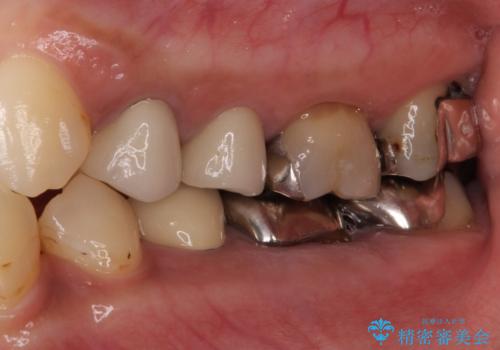

- 歯を削る量が少ないとの触れ込みで最近接着ブリッジを装着したものの、そのブリッジと歯の間に隙間ができているとのことで来院された患者様です。

歯の裏側を一層だけ削り、接着力に頼ったブリッジを装着してはみたものの、案の定咬む力に負けて、接着が剥がれてしまっていました。

歯を削る量は増えますが、より長い期間再治療なく使用していただくことを最優先に考え、フルカバレッジのオールセラミックブリッジにて補綴することとしました。

他にも、奥歯の銀歯の下にもむし歯が多くあり、痛みが生じていたため、根管治療などを行った上で、オールセラミッククラウンにて補綴治療することとしました。